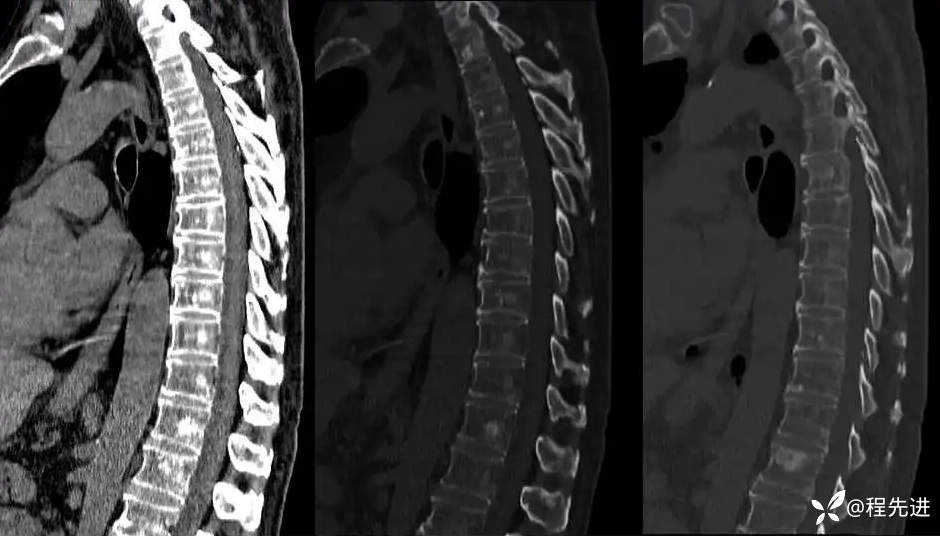

胸椎: